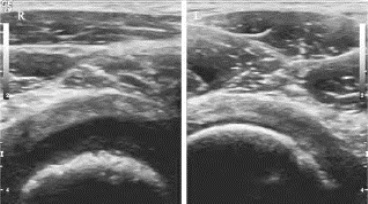

(1)二维超声:关节周围软组织肿胀增厚,关节腔内出现无回声区或低回声区,内回声不清晰,可有散在细小光点,脓肿形成(图35-9)。骨质破坏时,强回声骨质连续性中断,表面粗糙不平。

图35-9 关节腔积液声像图

左图为关节腔积液,右图为正常的关节腔